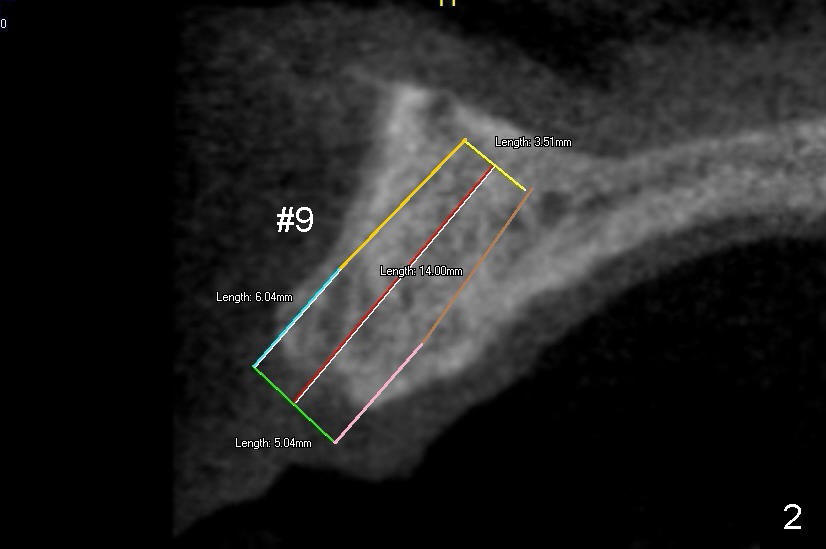

There are two types of implant design for the upper central incisors. The first one is to place implants as large as possible (Fig.1,2), i.e., place the implants in the middle of the alveolar bone, irrespective of the occlusion with the opposing.